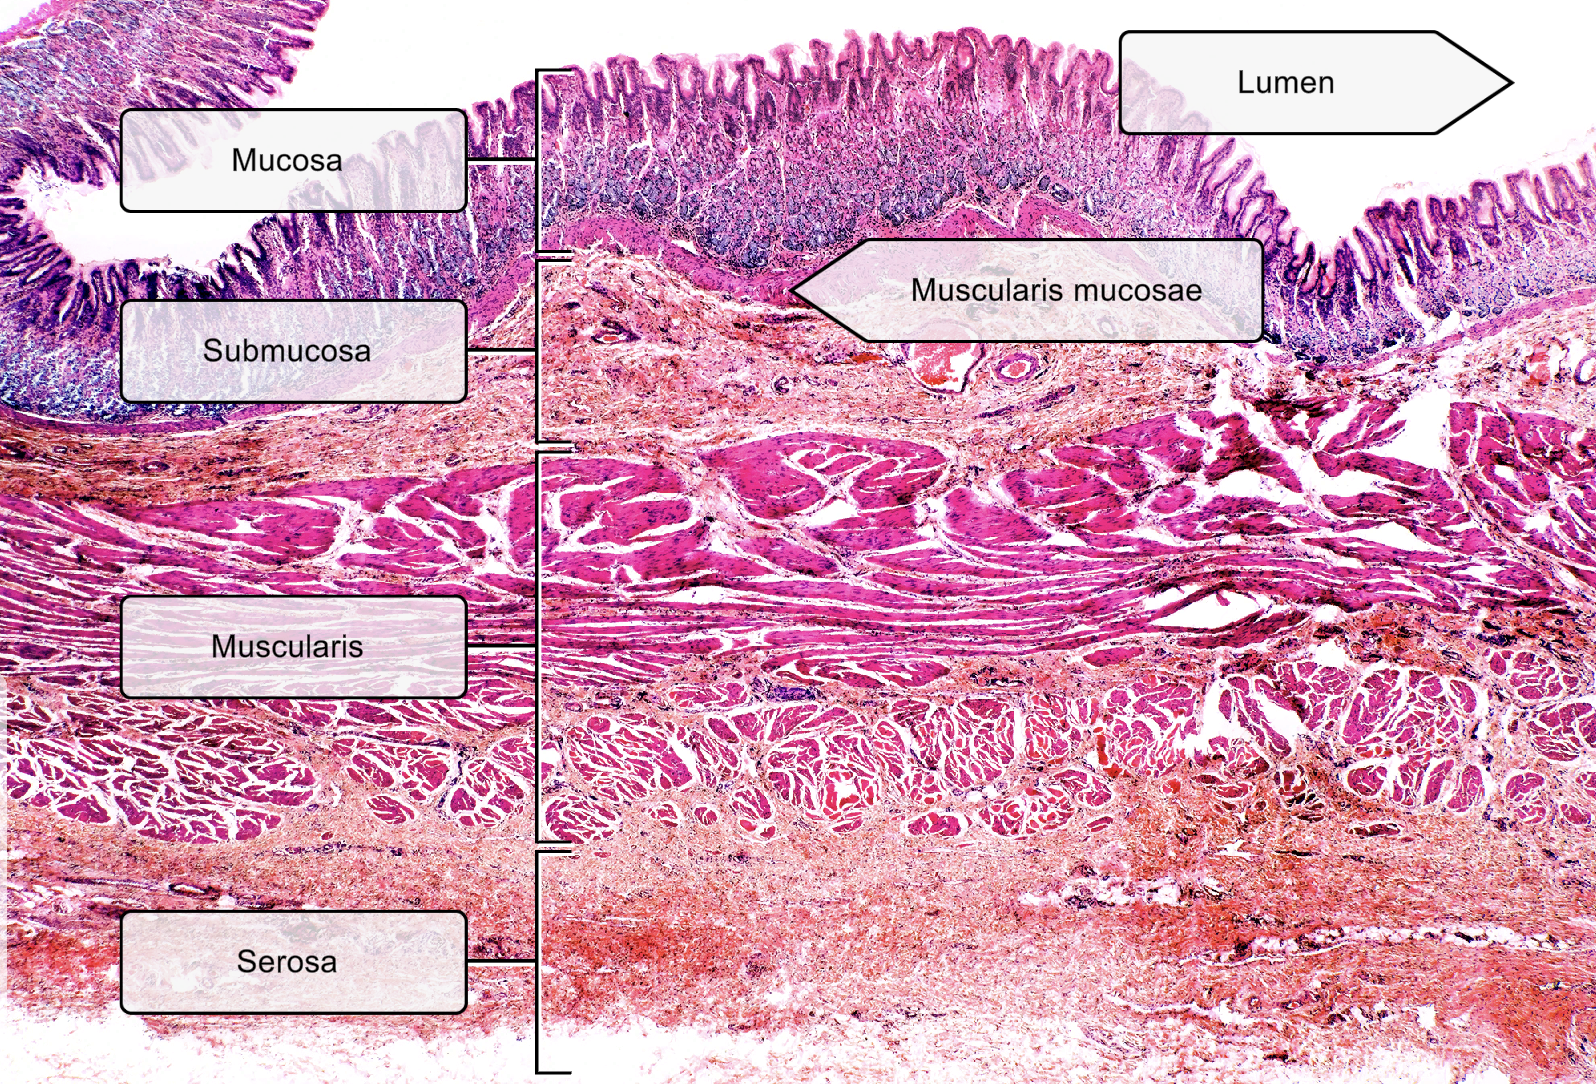

List the layers in the small intestine

Mucosa- ciliated pseudostratified columnar epithelium